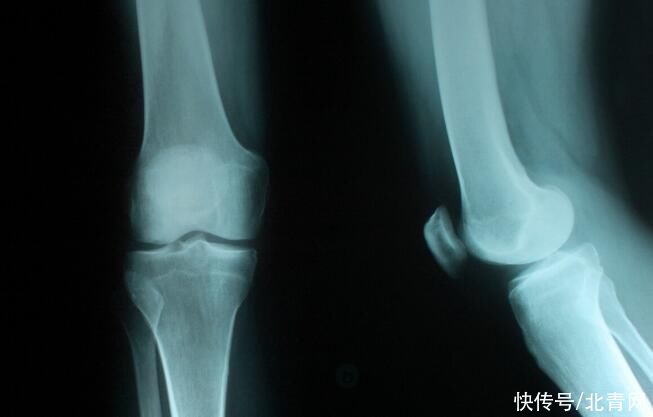

很多人都不知道榴莲的含钙量是非常可观的,经常吃榴莲,补钙效果很好,能够让骨骼更强健。想要预防骨质疏松的人,吃榴莲是不错的选择。

- 许多人|医生提醒经常腿疼的人,多吃4种食物,远离膝骨关节炎